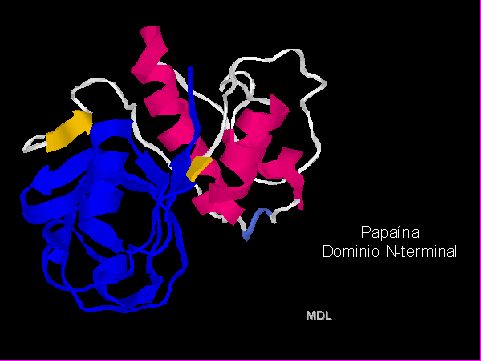

Como otro componente dentro del sistema químico-mecánico de remoción de tejidos cariados surge el Papacárie® en el 2003, UNINOVE (Universidad de São Paulo/Brasil), como un mecanismo de proteolisis enzimática del colágeno dentinario. Este producto está compuesto por Papaína, cloramina, azul de toluidina, conservante, espesante y vehículo. La enzima Papaína es una tiol-proteinasa, es decir, una enzima proteolítica cuyo centro activo posee un grupo -SH- . Se extrae del látex de la papaya o mamao verde (Carica papaya), es la responsable de las conocidas propiedades digestivas de dicha fruta y es empleada ampliamente en la industria alimenticia, farmacéutica y cosmética.

En la estructura de la Papaína (Figuras 13 y 14)11 se aprecian dos "ovillos" (dominios) separados por una zona sin estructura secundaria en particular. Así, el dominio 1, que corresponde aproximadamente a la mitad N-terminal de la molécula, presenta una estructura secundaria de tres alfa-hélices, mientras que el dominio 2 o C-terminal: tiene una estructura secundaria distinta (un meandro b antiparalelo y dos a-hélices). A menudo los dominios corresponden a diferentes funciones dentro de la misma proteína (por ejemplo, regiones catalíticas y regiones regulatorias) y casi siempre corresponden a tramos genéticos codificantes (exones) diferentes.

Fig. 14

La Papaína se identifica como una endoproteasa. Las proteasas con tiol (Stryer L.)12 ,13 son un grupo de enzimas ampliamente distribuido, que contiene un centro activo con cisteína, la cual realiza una función análoga a la de la serina 195 de la quimotripsina. La catálisis se realiza a través de un intermediario tioester y se halla facilitada por una cadena lateral de histidina próxima. Presenta propiedades: antiinflamatoria, bacteriostática y bactericida (Candido, 200114 ;Pereira, 2004 15).

Particularmente, la papaína es una tiol proteasa cuyo centro activo es Cis 25, His 159, y Asp 15816. Presenta una amplia actividad proteolítica ante las proteínas, péptidos de cadena corta, enlaces amida y ésteres de aminoácidos y se utiliza de manera muy extendida en el ámbito de la alimentación y la medicina. Su peso molecular es de 23,000 dalton y su pH óptimo es entre 3 y 7 el cual varía según el sustrato. Su número de clasificación es 3.4.22.2. Pertenece a la clase de las hidrolasas, tiene una amplia especificidad sobre las uniones peptídicas siendo una endopeptidasa (rompe enlaces peptídicos de sus sustratos que no están cerca de los extremos terminales de la proteína a romper).